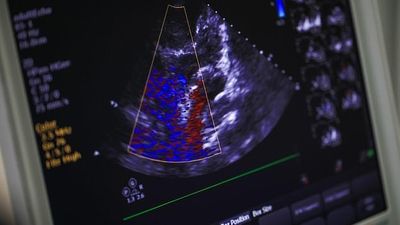

Sipas mediave të huaja, përcjell Telegrafi, më shumë se gjysma e pacientëve të infektuar në një spital të Britanisë së Madhe që iu nënshtruan skanimit në zemër, u përballën me disa ndryshime anormale.

Bëhet e ditur se një në tetë pacientë kishte shenja të ‘mosfunksionimit të plotë’ në zemrën e tyre, ndërsa mjekët nuk mund të gjenin ndonjë shpjegim tjetër përveç coronavirusit.

Studimi i kryer nga Fondacioni Britanik i Zemrës, shpreh shqetësimin se coronavirusi mund të shkaktojë dëme të përhapura në organet jetësore të pacientëve, madje te disa edhe disa probleme të tjera shëndetësore që mund të zgjasin me muaj ose edhe me vite pas infeksionit të coronavirusit.